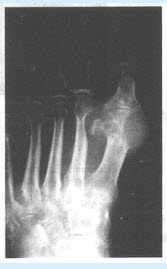

患者,男,56岁。左足肿痛2年。

第1题,共3个问题

(单选题)X线平片检查如图,考虑为何病()

A:痛风性关节炎

B:结核性关节炎

C:类风湿关节炎

D:化脓性关节炎

E:松毛虫性关节炎

F:风湿性关节炎

第2题,共3个问题

(单选题)为了明确诊断最需要做哪项检查()

A:查血沉

B:血常规

C:CT检查

D:血尿酸

E:MR检查

F:类风湿因子

第3题,共3个问题

(多选题)关于痛风性关节炎描述下列哪些正确()

A:95%男性发病,有家族遗传倾向

B:血清及体液中尿酸增加

C:潜伏期常无症状

D:关节肿痛呈非对称性结节样肿胀

E:皮下有痛风结节

F:常首先出现于第一跖趾关节,关节端出现边缘锐利的小囊状或穿凿状圆形或椭圆形骨缺损区,其边缘翘起突出颇具特征